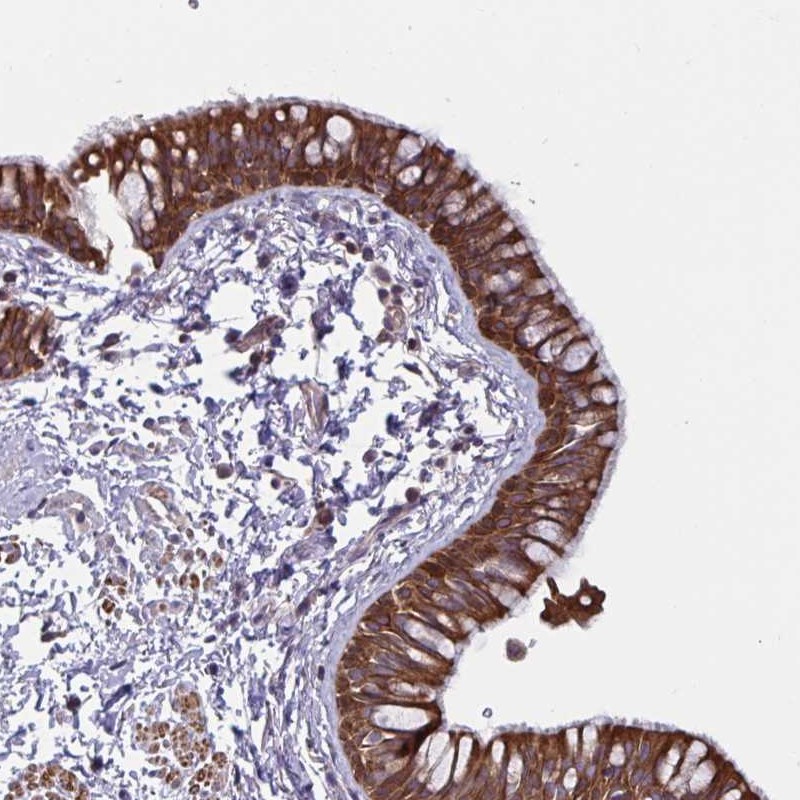

Immunohistochemical staining of human bronchus shows strong cytoplasmic and membranous positivity in respiratory epithelial cells.